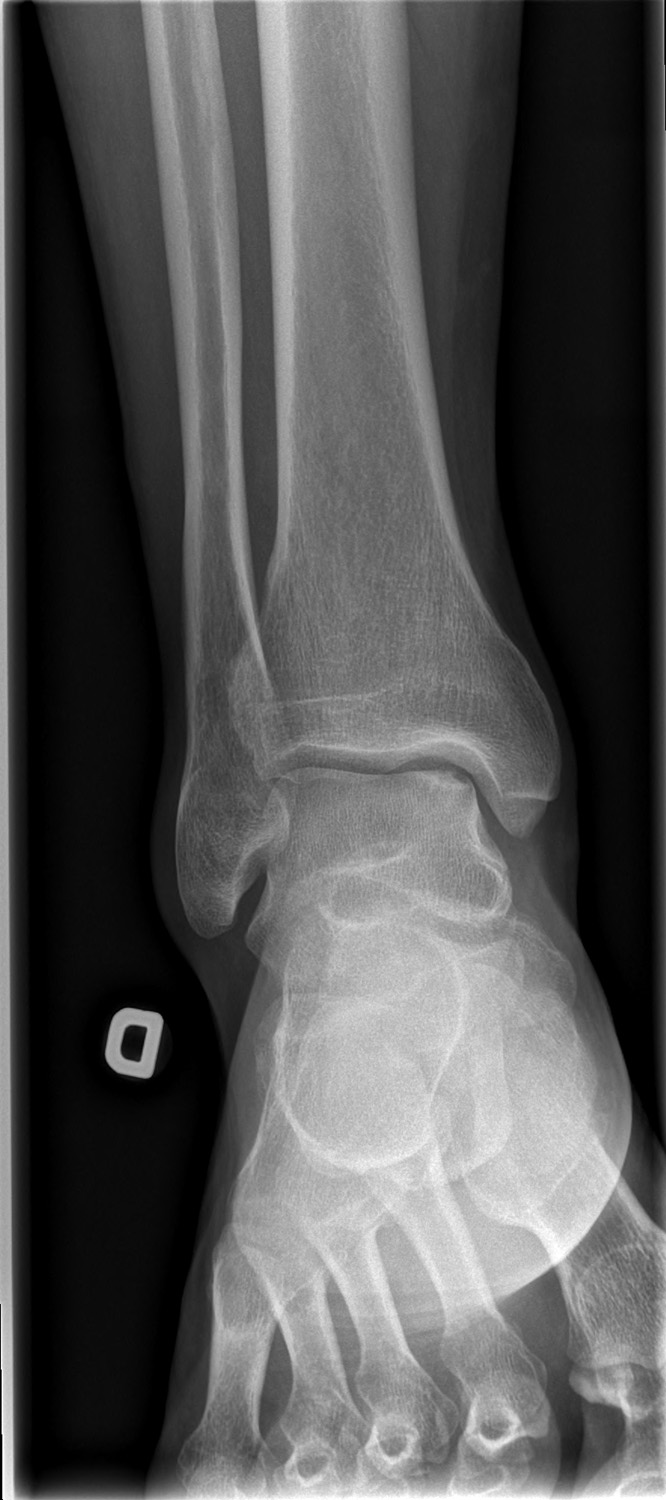

69-year-old male:

Persistent right ankle pain following a sprain.

Osteochondritis dissecans

Cortical defect and sclerosis of the superomedial talus compatible with an osteochondral lesion. Assessment of the fragment is impossible on these views, however, and the precise type cannot be acertained.